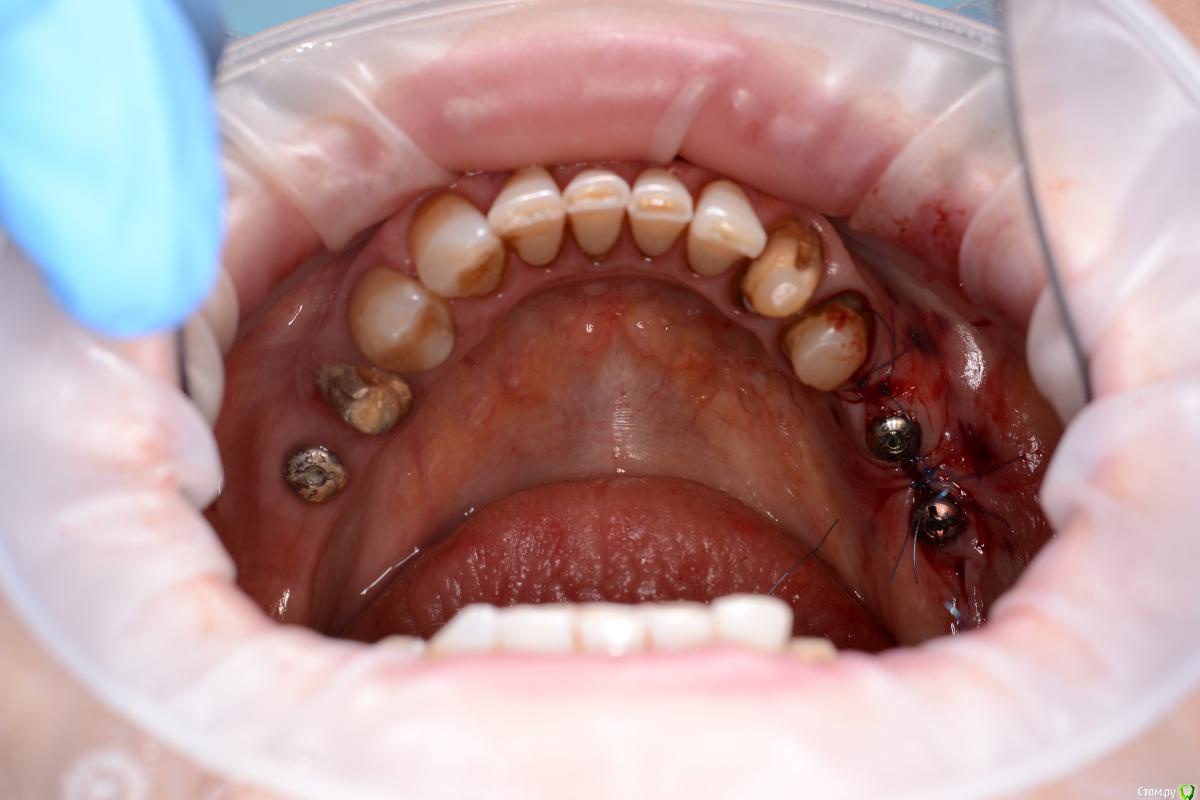

Sergiosse Опубликовано 10 июня, 2017 Поделиться Опубликовано 10 июня, 2017 (изменено) Под сетки "Mega-Oss" и поверх мембраны PRFВ такой ситуации планирую остемовскую сетку ставить .Пара вопросов Что лучше под нее Ауто или микст,насколько выше платформы импланта взять спейсер, ставить фдм или заглушку?После прф не прорезывается сетка ? Изменено 10 июня, 2017 пользователем Sergiosse Ссылка на комментарий